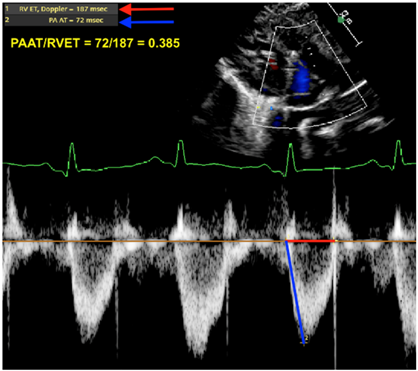

| Pulmonary artery acceleration time/right ventricular ejection time (PAAT/RVET) | This ratio provides some insight on the RV afterload. In a situation where the RV afterload is increased (either due to high pulmonary vascular resistance or other contributors—flow/pressure transmission), this ratio decreases. Ratio is measured from the pulsed wave (PW) Doppler envelope of the right ventricular outflow tract. A low ratio suggests an increased pulmonary afterload (abnormal < 0.31; some use a cutoff of <0.25) [26,27,28]. |

| PAAT/RVET | ![]() |

| Legend: The pulmonary artery acceleration time to the right ventricular ejection time is a ratio providing some insight on the RV afterload. In situations where the RV afterload is increased (either due to high pulmonary vascular resistance or other contributors—flow/pressure transmission), this ratio decreases. The pulsewave Doppler envelope of the RV outflow tract shifts from a parabolic shape to a more triangular shape with a steeper diastolic upstroke. Here, the ratio is 0.385 (abnormal < 0.31; some use a cutoff of <0.25). | |